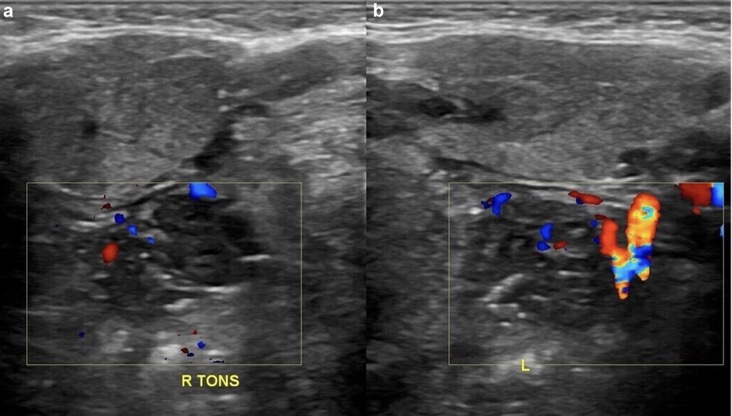

4. Augmentation de la vascularisation amygdalienne interne

EX: LYMPHOME DE BURKITT